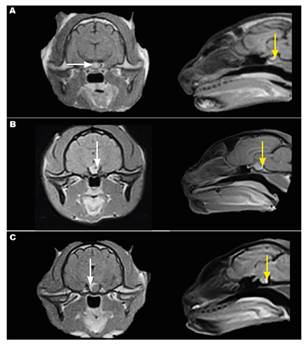

AT1-weighted magnetic resonance imaging (MRI) of the sellar region, following administration of the contrast medium (gadolinium), revealed increased pituitary size (5.7 mm width x 4.5 mm height-normal up to 5.0 mm width, and up to 3.3 mm height according to Feldman, 2015) for Case 1 (Figure 2A).

In turn, Case 2 showed a pituitary macroadenoma with suprasellar extension (7.6 mm length x 6.2 mm height), heterogeneous appearance, hyperintense rims and inner cystic hypointense areas (Figure 2B). Case 3 presented a 6.3 mm-diameter pituitary macroadenoma with granular appearance, partially surrounded by a hyperintense rim (Figure 2C). The MRI supplemented and confirmed AMG diagnosis in the three cats, thus defining the cause of IR.